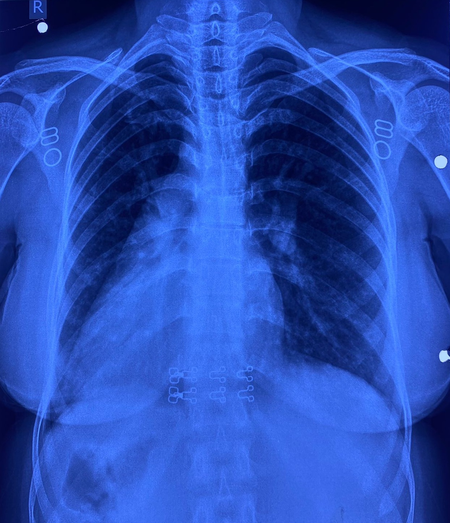

इस मरीज के सभी अंग सामान्य जगह के उलट यानी मिरर इमेज में थे। उसके दिल की जगह दाईं ओर थी, लिवर बाईं ओर, प्लीहा दाईं ओर और पेट भी दाईं ओर था। इसके साथ ही मरीज में जन्मजात आंशिक एट्रियोवेंट्रिकुलर कैनाल दोष जैसी जन्मजात हृदय रोग की समस्या भी थी।

सर्जरी के दौरान चिकित्सा टीम ने अत्यंत सावधानी बरतते हुए मरीज के हृदय दोष का सफल उपचार किया। मात्र 4 सेंटीमीटर के सूक्ष्म 'इन्फ्रामैमरी' चीरे के जरिए यह जटिल प्रक्रिया संपन्न की गई। ऑपरेशन के दौरान हृदय की कार्यप्रणाली को सुचारू रखने के लिए शरीर की बाहरी नसों की सहायता से 'कार्डियोपल्मोनरी बाईपास मशीन' का उपयोग किया गया। हृदय के दोष को ठीक करने के लिए मरीज की अपनी 'पेरिकार्डियम' (हृदय की सुरक्षा झिल्ली) से पैच तैयार किया गया और उसे बेहद बारीक टांकों के जरिए सटीक स्थान पर लगाया गया, ताकि हृदय के वाल्व और कंडक्शन सिस्टम को कोई क्षति न पहुंचे। सर्जरी के बाद मरीज की रिकवरी बहुत ही सहज रही और अब वह अस्पताल से जाने के लिए पूरी तरह फिट है। इकोकार्डियोग्राफी ने भी सफल सर्जरी की पुष्टि की।

इस सर्जरी में कई चुनौतियां थीं। सबसे बड़ी चुनौती यह थी कि जन्मजात हृदय दोष, वाल्व और संवेदनशील कंडक्शन सिस्टम के अत्यंत निकट था। इसके अतिरिक्त, रक्त वाहिकाओं की 'मिरर इमेज' (विपरीत दिशा) स्थिति ने सर्जरी को और भी पेचीदा बना दिया था। महज 4 सेंटीमीटर के छोटे चीरे के माध्यम से उपकरणों को संभालना और सूक्ष्म टांके लगाना तकनीकी रूप से बेहद कठिन कार्य था। मरीज को हृदय–फेफड़ों की मशीन के माध्यम से बायपास करना पड़ा, जिससे टीम की विशेषज्ञता और अनुभव की जरूरत थी।

साइटस इन्वर्सस अपने आप में बहुत ही दुर्लभ है और इसके साथ आंशिक एट्रियोवेंट्रिकुलर कैनाल दोष होना और भी कम होता है। आम तौर पर ऐसी सर्जरी में सीने की हड्डी काटनी पड़ती है, लेकिन इस केस में सिर्फ छोटे कॉस्मेटिक चीरे से सर्जरी की गई, जिससे यह दुनिया की पहली सर्जरी बन गई। मरीज रमबाई और उनके परिवार ने डॉ. नरेन्द्र सिंह झाझड़िया और पूरी टीम का दिल से धन्यवाद किया।